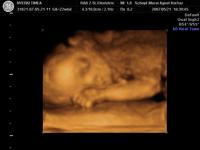

Megjártuk tegnap a 4d-t. Igazatok volt.Szuper volt látni a kis Törrpét. Az ujjacskáit, lábiját, kis pofit. Párom szerint már most is látni, hogy a nózit tőle örökölte. :D

Mi a Schöpf-Méreiben voltunk. (www.mamakalauz.hu)

18 percet vettek fel dvd-re. Kinyomtattak 4 szines képet és 1 darab 2 d-st, és az internetes honlapjukra még feltettek 20 képet amit 30 napig le lehet tölteni.Ár 13000

Ha mégegyszer akarunk menni akkor 5000 forint kedvezményt kapunk.

A hölgy nagyon kedves volt, mindent elmondott és megmutogatott. A rendelő pedig pontosan az amit az interneten feltettek képet.

Megpróbálok pár képet feltenni. Kép Tornászbajnok Kép Szundi Kép Szundi méhlepényes takaróval